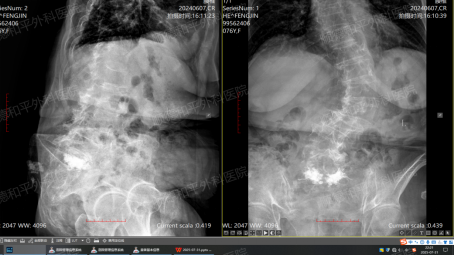

4月15日,何阿姨因“反复腰痛1个月”入院,诊断结果显示为“老年性骨质疏松伴病理性骨折”。两天后,医院为她实施了S1椎体压缩性骨折椎体成形术——通过微创手术将骨水泥注入骨折椎体,以稳定脊柱、缓解疼痛。术后摄片显示骨水泥填充成功,李奶奶的疼痛感一度减轻,便回家修养。

然而,两个月后的6月7日,腰背酸胀痛再次袭来,伴随全身多处牵扯痛,腰椎活动受限。复查时,医生发现她腰部及双侧季肋区触压疼痛明显,虽双下肢功能正常,但骨折后的慢性疼痛仍如影随形。7月31日,第三次入院时,影像报告更显示骶3-5椎体前缘皱褶、L3/4至L5/S1椎间盘变性膨出,椎管狭窄、硬脊膜囊受压……“重度骨质疏松症”的诊断背后,是患者与骨折反复抗争的漫长历程。这也意味着,在骨质疏松的持续影响下,她的脊柱退变仍在进展,新的损伤风险时刻存在。